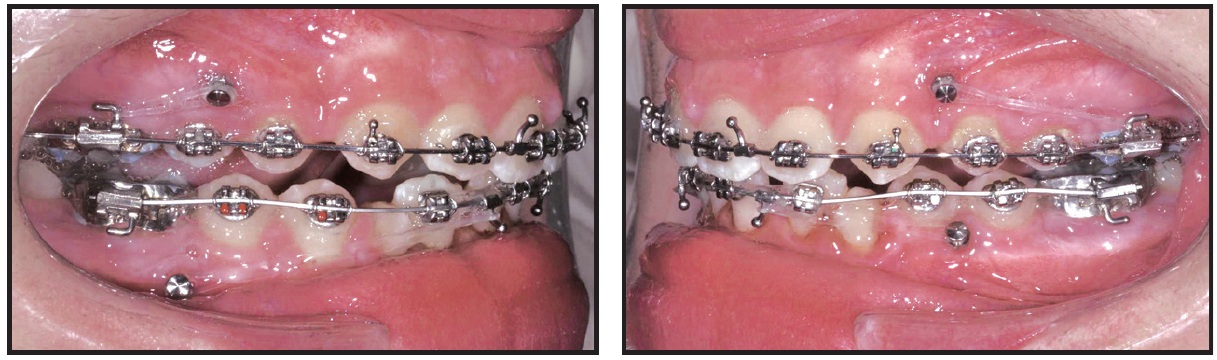

Preadjusted .022" × .028" brackets*** were placed in the upper arch, and an .014" nickel titanium archwire was used to correct the upper incisor inclination and the scissor bite (Fig. 2). After five months of treatment, a Herbst appliance with four 1.4mm × 6mm TADs† (H4T) was placed (Fig. 3). In the lower arch, one miniscrew was inserted between the right first permanent molar and second premolar and the other between the left first and second premolars. Auxiliary buttons were bonded to the buccal surfaces of the canines, and elastic chains were attached to the miniscrews to retrocline the lower incisors and promote mandibular protraction. In the upper arch, a miniscrew was inserted between the first and second premolars on each side, and elastic chains were attached between the miniscrews and an .018" × .022" stainless steel archwire for vertical control.

Fig. 4 Failed upper left TAD replaced after 11 days with TAD between canine and first premolar.